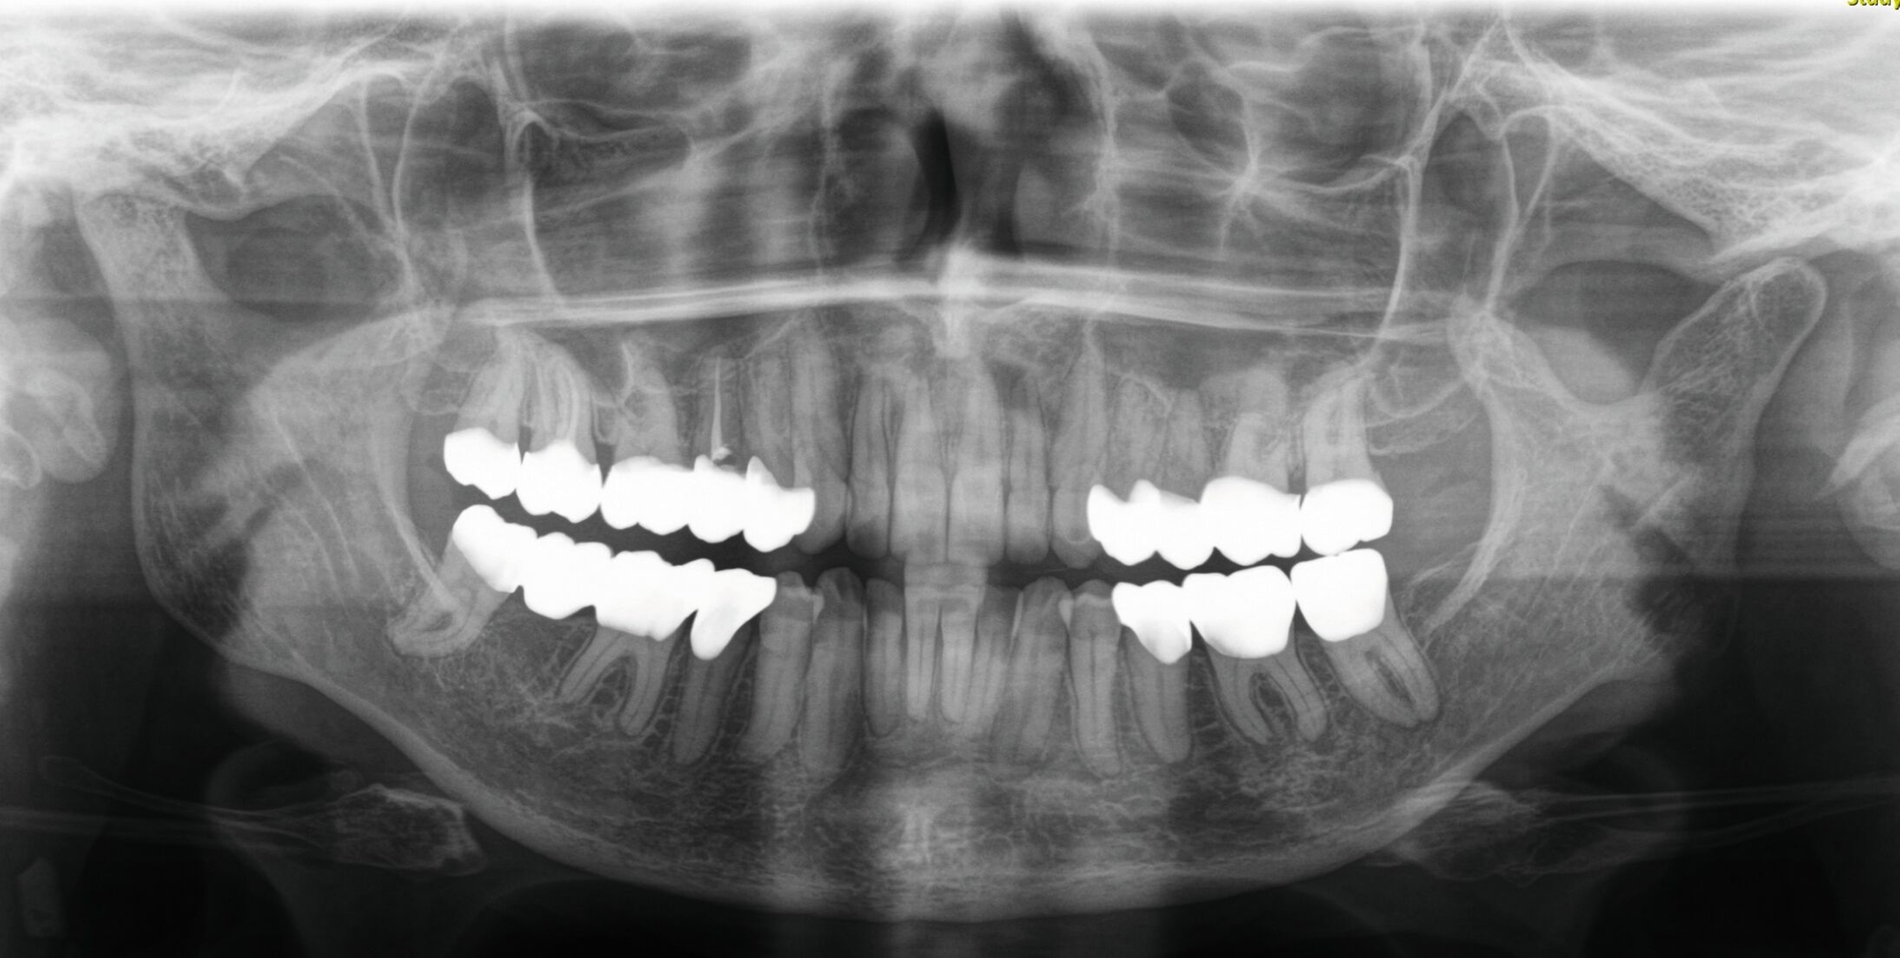

Klinisch zeigten sich diverse großflächig, mehrheitlich mit Amalgam gefüllte Seitenzähne, suffiziente endodontische Behandlungen an den Zähnen 16 und 14 sowie intakte Kronen an den Zähnen 16 und 48 (Abbildung 2). Ein Parodontaler Screening-Index (PSI) wurde erhoben (1-1-0-0-2-1), der stabile Verhältnisse nachwies. Das funktionelle CMD-Screening zeigte eine nicht-druckdolente Kaumuskulatur sowie eine uneingeschränkte Mundöffnung ohne Reiben und Knacken.

Im Rahmen der Konsultation der Mund-, Kiefer- und Gesichtschirurgie und der Kieferorthopädie erfolgte eine erneute radiologische Bildgebung (Abbildung 4). Die Patientin wurde im Anschluss beraten, dass eine Re-Osteotomie des ehemals frakturierten und nun in Fehlstellung verheilten Collumsegments links ihr Okklusionsproblem adäquat lösen könnte. Ebenso sei eine orthognathe Umstellungsosteotomie möglich. Nach ausführlicher Aufklärung entschied sich die Patientin allerdings gegen eine chirurgisch-kieferorthopädische und für eine rein prothetische Lösung. Die Patientin hatte derart Angst vor einem erneuten chirurgischen Eingriff, dass sie selbst die Aussicht auf eine längere und invasivere prothetische Behandlungsphase nicht abschreckte.